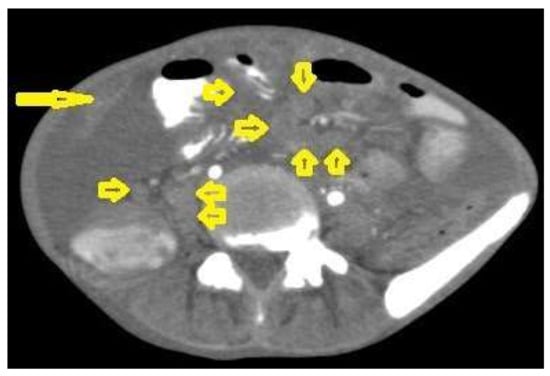

• Tuberculous peritonitis is the most common clinical presentation of abdominal TB. It involves the peritoneal cavity, mesentrium, and omentum. Peritonitis is believed to be originated from hematogenous spread or secondary to LN rupture, gastrointestinal dissemination, or fallopian-tube involvement [46,47]. Tuberculous peritonitis has three radiological patterns:

• Wet peritonitis (Figure 21) is the most common type that is characterized by free or loculated ascites with or without peritoneal thickening [46,47].

• Fibrotic peritonitis (Figure 22) is characterized by remarkable omental and mesenteric thickening forming cake-like masses with bowel loops enlargement and matting that can be seen by CT or ultrasound. [46,47].

Figure 21. Wet peritonitis in a 16-year-old man with cachexia and loss of appetite. Selected axial abdominal images show marked relatively dense ascites and gross thickened omentum with faint enhancement of peritoneal reflections (long arrows) with multiple enlarged mesenteric and upper paraortic conglomerated lymph nodes (short arrows) with slight homogeneous enhancement.

Figure 22. Fibrotic peritonitis in a 20-year-old man with fatigue, abdominal distension, and loss of appetite. Selected axial images of abdominal CT show remarkable omental thickening, forming cake-like masses (arrows) with faint enhancement and mild smooth thickening of peritoneal reflections associated with mild-to-moderate dense ascites and several low-attenuation mesenteric lymph nodes that are challenging to be distinguished from small bowel loops.